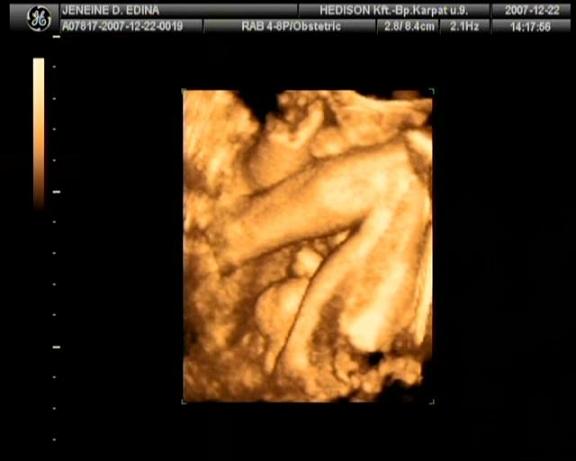

2007.december 25.-re voltunk kiírva. Védőnőm 12. 07.-én pénteken jött hozzánk azzal a céllal, hogy összeírjuk mindazt ami szükséges a nagy napra. Szombaton megvettük a nadrágpelenkát és a popsitörlőt, így már mindent beszereztünk babánknak. Vasárnap még hab mesefigurákat festettünk férjemmel. Nem gondoltuk, hogy valami elkezdődik pocakomban. Este hamar kidöltem,

Pár perccel később orvosom újból megvizsgált és mondta nagyon vaskos még a méhszáj (segített ezen), de ez nem csoda, hiszen még csak a 37. hétben vagyok. Mondta, hogy feküdjek a jobb oldalamra és akkor az az oldal is nyomás alatt lesz. Így is történt, közben elmagyarázta, mi fog történni rövid időn belül. Úgy is lett! Férjemnek megmutatta, hogy már látszik Lara feje!

Kaptam Augmentint, mert 37.5 lett a testhőmérsékletem. Orvosom elmagyarázta a nyomástechnikát. Egy-két nyomás után kaptam gátmasszázst és gátmetszést, majd szóltak a gyermekorvosnak, hogy jöhet hozzánk „jön a baba”. Ettől kezdve a negyedik nekifutásra megszületett Lara babánk 21.40-kor (3310g 49 cm), aki nagyon édes! Apa elvágta a köldökzsinórt.